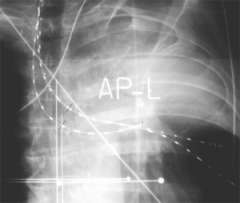

AP (front) radiograph of three treatment catheters placed in the bronchi to encompass the lesion that is obstructing air from reaching the left upper lobe of this patient. After the treatment, the catheters are removed, the patient recovers quickly and then goes home. Usually, three or four treatments are given. Successful treatment opens the bronchi, (improving breathing), and reduces bleeding (hemoptysis).